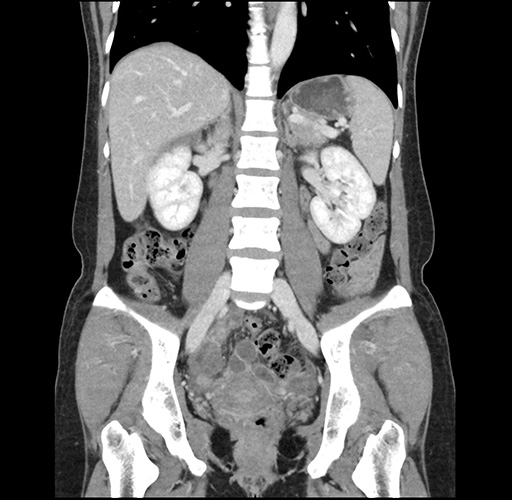

Imaging Analysis

Look through the patient's CT scan to identify any areas of concern for the necessary procedure.

Based on your CT findings, which issue(s) would give reason for "planned slowing down moment(s)" in this case?

Considering a standard left lateral sectionectomy procedure, what step(s) of the operation would you do differently in this case ?